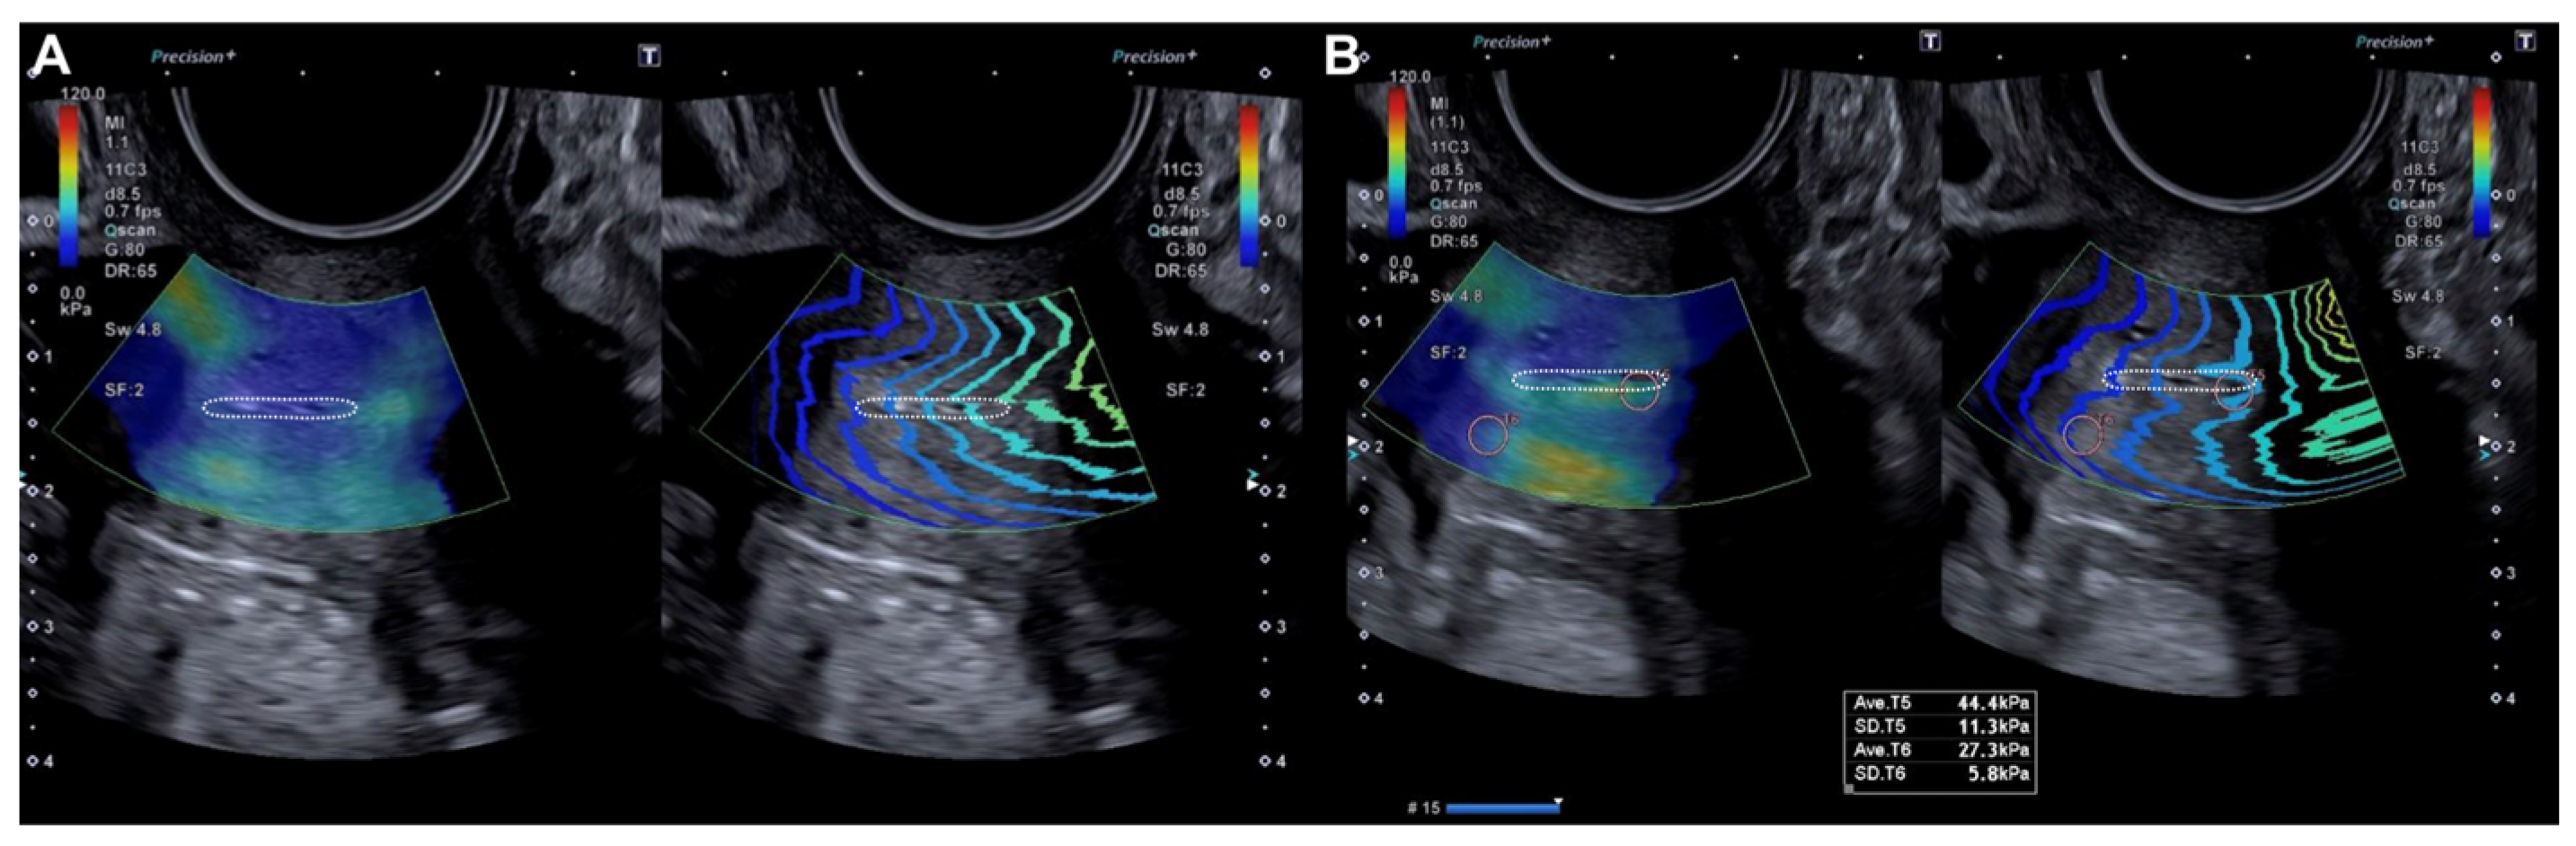

2.2.2. Evaluation Using SonoElastoColposcopy

| Exocervix (kPa) | 19.98 (±9.29) | 105.42 (±36.32) | p < 0.0001 |

| Endocervix (kPa) | 18.5 (±9.07) | 109.8 (±40.86) | p < 0.0001 |